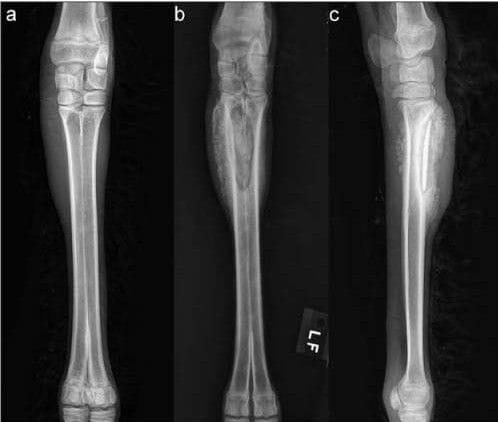

Radiographic images of the left forelimb of a 3-month-old male alpaca with osseous sequestration. A—Dorsopalmar view obtained by the referring veterinarian 7 days after the cria began to have signs of lameness in the affected limb. Notice the soft tissue swelling surrounding the proximal aspect of the left fused metacarpal bones without evidence of bony lesions. B—Dorsopalmar view of the same left forelimb (LF) 13 days later, revealing a cortical sequestrum of the dorsomedial aspect of the fused metacarpal bones. C—Lateromedial view obtained at the same time as the view in panel B. Physical examination of the cria failed to reveal signs of trauma.